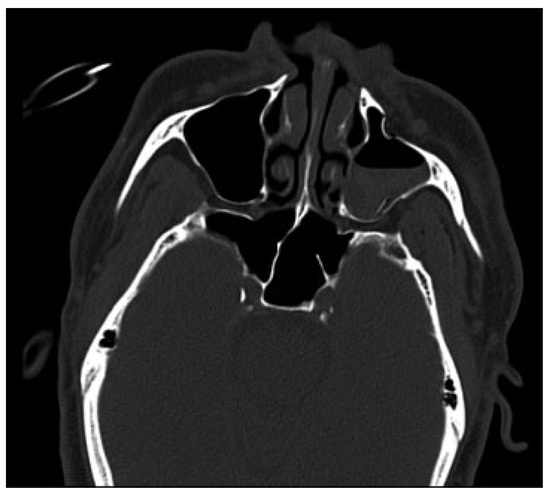

Subsequently, the diagnosis was made of a left zygomaticomaxillary complex (ZMC) fracture with associated SOFS caused by compression of the fissure by bony segments. After discussion of treatment options, an open reduction with internal fixation of the left ZMC fracture was performed under general anesthesia using lateral brow and a maxillary vestibular incision with hopes of minimizing the bony impingement of the superior orbital fissure. The patient was given a perioperative dexamethasone taper beginning with an immediate preoperative dose of 10 mg. A postoperative maxillofacial CT was obtained to evaluate the reduction and reassess the left superior orbital fissure (Figure 5 and Figure 6). The patient was followed weekly by the Oral and Maxillofacial Surgery service as an outpatient. The patient’s SOFS resolved completely (Figure 7).

Figure 5. Postoperative maxillofacial computed tomography showing reduction of the left zygomaticomaxillary complex fractures.